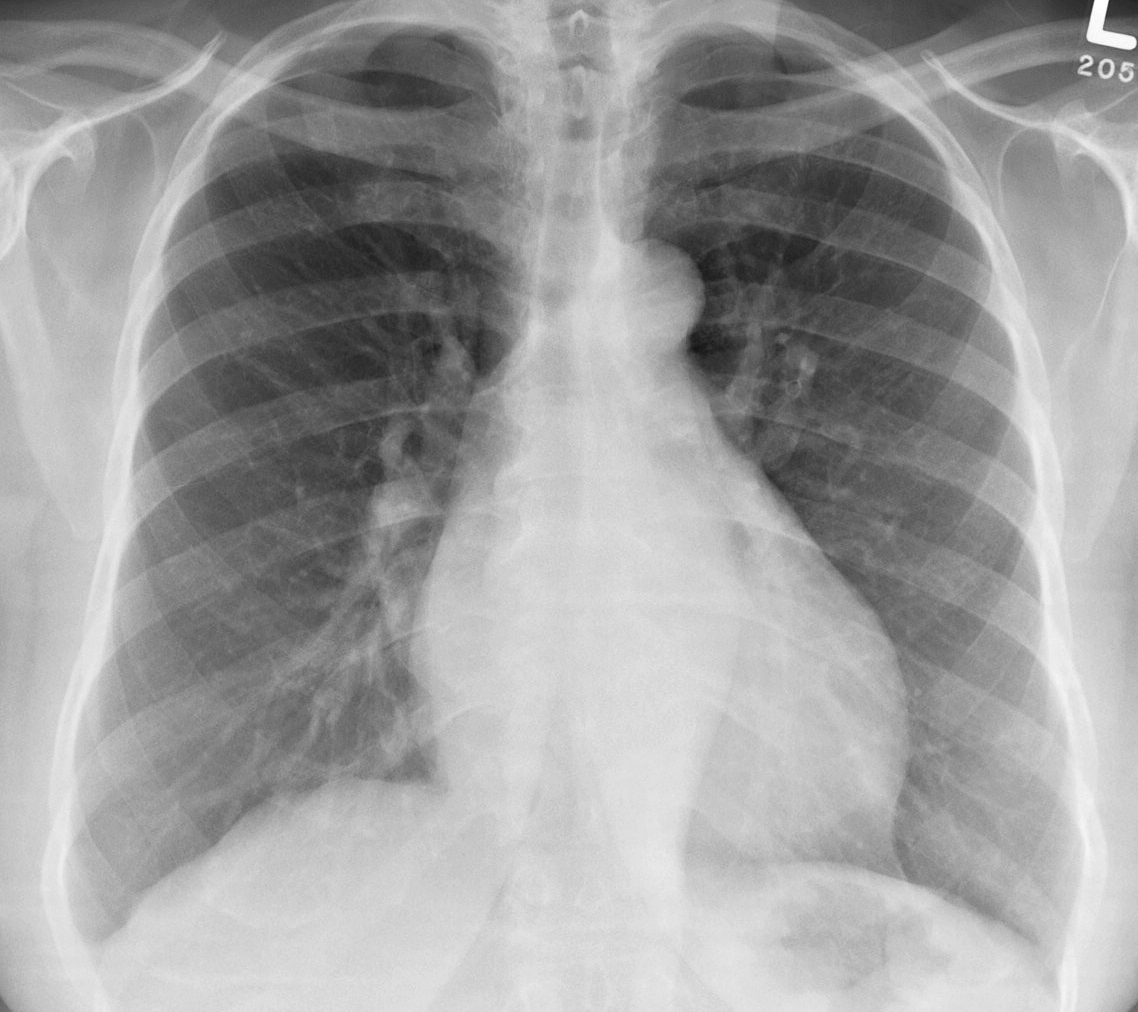

Gallery Cardiac Mitral Valve Disease Mitral Valve Disease Case 10 PA

Mitral Valve Disease

Case 10 PA